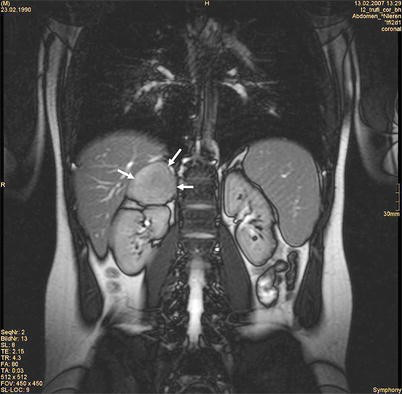

- Adrenal: CT/MRT Abdomen

| Maligne | Adrenokortikales Karzinom, Metastasen (z. B. Lunge, Mamma, Niere, Melanom) | Oft große Tumoren, Wachstum, evtl. hormonaktiv | > 4–6 cm oder suspekt → Adrenalektomie |

CT/MRT: Adenom < 10 HU (fettreich), Karzinom > 20 HU, suspekt bei schnellem Wachstum